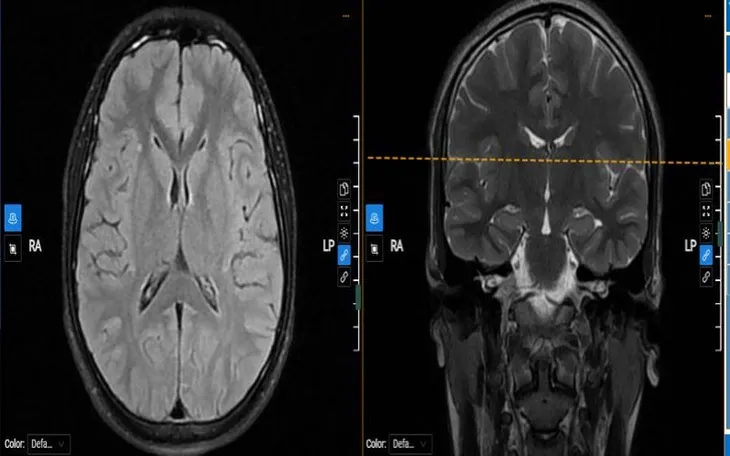

Kết quả điện não đồ ghi nhận các hoạt động kịch phát ở bán cầu phải, lan sang cả hai bên. Hình ảnh cộng hưởng từ não phát hiện vài nốt mất myelin rải rác. Các xét nghiệm máu và thăm dò tim mạch không phát hiện bất thường nguy hiểm. Từ đó, các bác sĩ chẩn đoán động kinh khởi phát cục bộ và kê thuốc chống co giật điều trị ngoại trú.

Để chẩn đoán chính xác, cần kết hợp thăm khám lâm sàng với các kỹ thuật như điện não đồ, cộng hưởng từ sọ não - mạch máu não, xét nghiệm máu và đánh giá tim mạch.